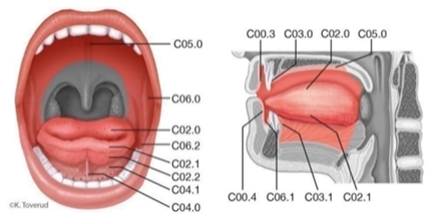

Med hode/hals-kreft forstås kreft i leppe, munnhule, nese- og bihuler, svelg, strupe og spyttkjertler. Lymfeknutemetastaser på halsen med ukjent utgangspunkt hører også inn under begrepet hode-/halskreft. Histologisk dreier det seg om plateepitelkarsinom (PEC) (ca. 90 %) og varianter av adenokarsinom (ca. 10 %). Svulstenes nære relasjon til kritiske strukturer gjør behandlingen utfordrende, og krever et tett tverrfaglig samarbeid mellom ØNH-, kjeve- og plastikk-kirurger, onkologer, radiologer, patologer, sykepleiere, stråleterapeuter, fysikere, kliniske ernæringsfysiologer og logopeder. Oppfølging etter primærbehandling kan involvere fastleger, tannleger og kommunale rehabiliterings- og omsorgstjenester.

I denne handlingsplanen omfatter begrepet hode-hals-kreft maligne svulster i følgende lokalisasjoner: Munnhule, svelg, strupe, nese/bihuler og spyttkjertler, samt lymfeknutemetastaser på hals uten kjent utgangspunkt og avansert hudkreft i hode-hals-regionen.